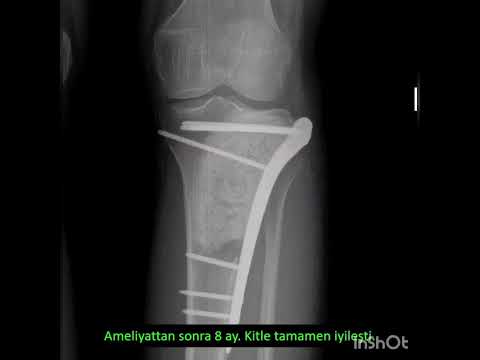

Doğru tedavi ancak doğru tanı konarak yapılabilir. Tedavide temel nokta, çok iyi planlanmış bir ameliyattır. Bu ameliyat bazen basitçe yapılabileceği gibi bazen de damar cerrahı, plastik cerrah, omurga cerrahı ve genel cerrahi gibi diğer branşların da operasyona dahil olmasını gerektirecek tarzda ağır ve kompleks operasyonlar şeklinde de olabilir. Ancak işin başında ortopedik onkolog olmalı ve tüm süreci doğru şekilde yönetmelidir. Aksi halde hasta uzvunu ya da hayatını kaybedebilir.

Ameliyat sonrası tümör hastasını neler bekler?

İyi planlanmış ve doğru şekilde ameliyatı yapılmış bir hasta kendisini birkaç günde toparlar ve günlük yaşantısına döner. Ağır vakalarda bu süreç uzayabilir. Ne olursa olsun ameliyattan önce hastaya bilgi verilir ve olası komplikasyonlar detaylıca anlatılır. Hastanın kafasındaki soru işaretleri ameliyat öncesi giderilir. Aksi her durum başarı şansını düşürecektir.